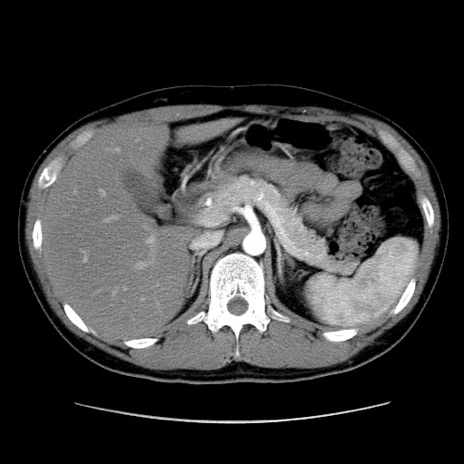

症例36(横断像)

【症例】20歳代 男性

【主訴】心窩部痛

【現病歴】今朝より上腹部痛あり。一旦軽快していたが再度出現したため救急要請。昨日夕に白身の魚を含む刺身を食べた。

【身体所見】BP 136/89mmHg、HR 74/min、BT 37.0℃、腹部:膨満、軟、心窩部に圧痛あり。反跳痛なし、筋性防御なし、腸雑音やや亢進あり。

【データ】WBC 17700、CRP 0.48